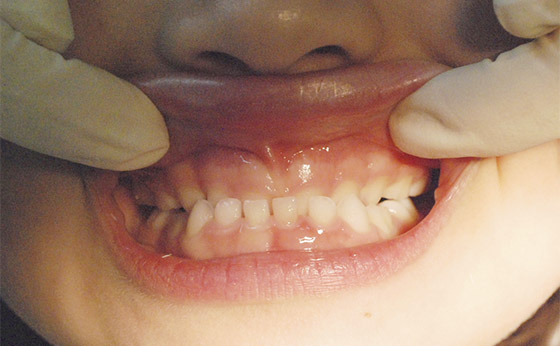

症例01 - 小児歯列矯正

ビフォー

1本だけ前歯が裏側に

アフター

この場合はマウスピースを作成して3か月。

とりあえずは前に出てきました。この後はしばらくは経過観察です。費用は成功報酬12,000円頂きました。